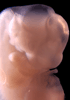

Carnegie Stage 15 (33 post-ovulatory days)

Most embryos at stage 15 are approximately 33 postovulatory days old and measure 7-9 mm in length. Distinguishing criteria for this stage include the appearance of nasal pits and hand plates. The lens vesicles are closed.